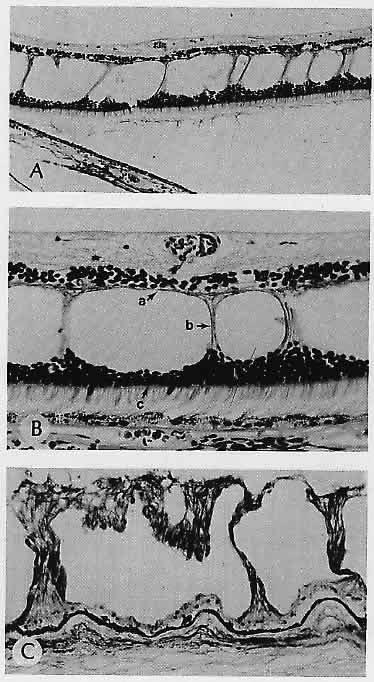

in the Prader-Willi syndrome. Am J Ophthalmol 94:328, 1982 7. Lloyd WC III, Eagle RC Jr, Shields JA et al: Congenital hypertrophy of the retinal pigment epithelium: Electron microscopic

and morphometric observations. Ophthalmology 97: 1052, 1990 8. Traboulsi El, Maumenee IH, Krush AJ et al: Pigmented ocular fundus lesions in the inherited gastrointestinal polyposis

syndromes and in hereditary nonpolyposis colorectal cancer. Ophthalmology 95:964, 1988 9. Munden PM, Sobol WM, Weingeist TA: Ocular findings in Turcot syndrome (glioma-polyposis). Ophthalmology 98:111, 1991 10. Traboulsi El, Maumenee IH, Krush AJ et al: Congenital hypertrophy of the retinal pigment epithelium predicts colorectal

polyposis in Gardner's syndrome. Arch Ophthalmol 108:525, 1990 11. Pagon RA: Ocular coloboma. Surv Ophthalmol 25:223, 1981 12. Fulton AB, Craft JL, Howard RO, Albert DM: Human retinal dysplasia. Am J Ophthalmol 85:690, 1978 13. Lahav M, Albert DM, Wyand S: Clinical and histopathologic classification of retinal dysplasia. Am J Ophthalmol 75:648, 1973 14. Kalina RE: A histopathologic postmortem and clinical study of peripheral retinal folds